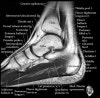

- Axial section

Axial PD fat suppression evaluates the tendons and ligaments of the ankle particularly after acute/subacute injuries. It also is sensitive to talar dome osteochondral defects. Alternatively, a T2 sequence can be used to eliminate magic angle artifact that may occur as the tendons travel around the malleolar turns.

Tibiofibular ligaments

Lateral ankle ligaments

Deltoid and spling ligaments

Tendon(Achilles, Medial, Lateral, Anterior)